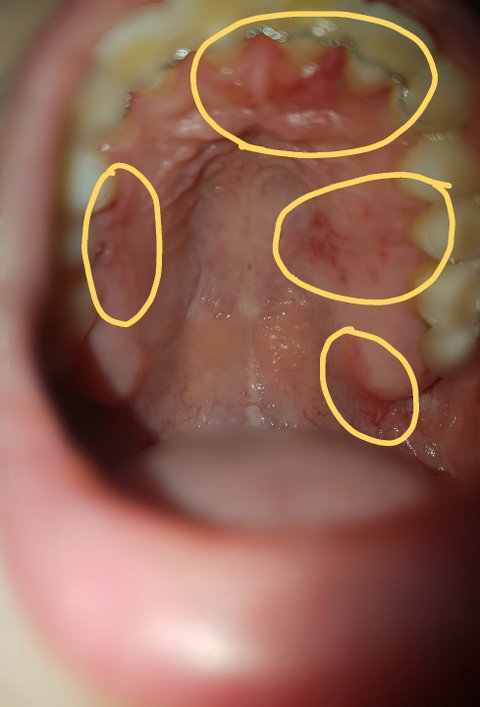

그리고 낮잠을 자고 일어나니, 가운데 윗 잇몸도 심각하게 붓고 오른쪽 윗 잇몸은 벗겨지고 있었으며, 전체적으로 발갛게 부어있었습니다.

다음은 피해사진입니다.

#피해자1

-4월 30일 월요일 낮

-4월 30일 월요일 밤

-5월 1일 화요일 아침